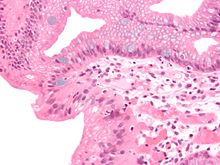

Both macroscopic (from endoscopy) and microscopic positive findings are required to make a diagnosis. Barrett's esophagus is marked by the presence of columnar epithelia in the lower esophagus, replacing the normal squamous cell epithelium—an example of metaplasia. The secretory columnar epithelium may be more able to withstand the erosive action of the gastric secretions; however, this metaplasia confers an increased risk of adenocarcinoma.[15]

The presence of goblet cells, called intestinal metaplasia, is necessary to make a diagnosis of Barrett's esophagus. This frequently occurs in the presence of other metaplastic columnar cells, but only the presence of goblet cells is diagnostic. The metaplasia is grossly visible through a gastroscope, but biopsy specimens must be examined under a microscope to determine whether cells are gastric or colonic in nature. Colonic metaplasia is usually identified by finding goblet cells in the epithelium and is necessary for the true diagnosis.[citation needed]

Many histologic mimics of Barrett's esophagus are known (i.e. goblet cells occurring in the transitional epithelium of normal esophageal submucosal gland ducts, "pseudogoblet cells" in which abundant foveolar [gastric] type mucin simulates the acid mucin true goblet cells). Assessment of relationship to submucosal glands and transitional-type epithelium with examination of multiple levels through the tissue may allow the pathologist to reliably distinguish between goblet cells of submucosal gland ducts and true Barrett's esophagus (specialized columnar metaplasia). The histochemical stain Alcian blue pH 2.5 is also frequently used to distinguish true intestinal-type mucins from their histologic mimics. Recently, immunohistochemical analysis with antibodies to CDX-2 (specific for mid and hindgut intestinal derivation) has also been used to identify true intestinal-type metaplastic cells. The protein AGR2 is elevated in Barrett's esophagus[17] and can be used as a biomarker for distinguishing Barrett epithelium from normal esophageal epithelium.[18]